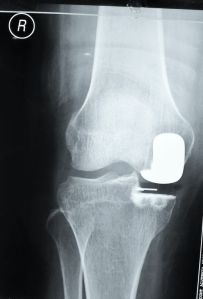

What Did I Do for this Patient?

This patient had severe pain and swelling of her right knee for about 3 months before consulting me. She is 56 years old.

She has tried pain killers, physiotherapy and use of crutches but her condition did not improve.

I performed a partial knee replacement for her.

Her pain improved significantly after the surgery and she was able to walk almost immediately.